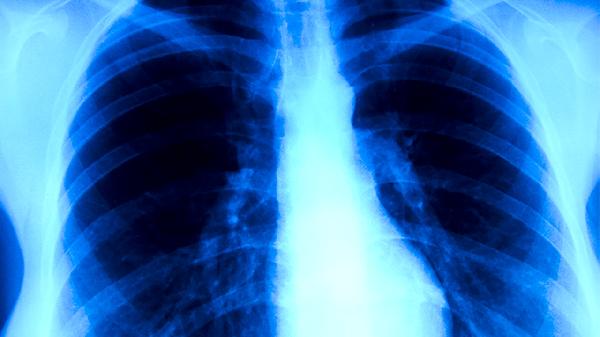

肺结核胸部X线常见斑片状阴影、空洞形成和钙化灶,病变多呈多形性改变。肺癌影像学表现为团块状阴影,边缘可有分叶或毛刺,可能伴随肺不张或胸腔积液。增强CT中肺结核病灶强化不明显,肺癌多呈明显强化。